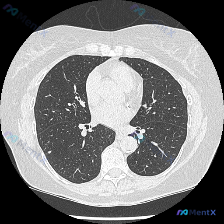

双肺上叶对称磨玻璃影:过敏性肺炎还是非典型病原体感染?

看到一个胸部CT肺窗的影像资料,整理了一下思路,跟大家分享讨论。

- 影像检查:胸部CT肺窗横断面,显示双肺上叶外周带对称性分布的磨玻璃影,边界模糊。无实变、空洞或钙化,气道通畅,胸膜光滑,无胸腔积液。

- 影像特点:对称性、上叶外周带分布的磨玻璃影。

- 过敏性肺炎:对称性、上叶外周带分布的磨玻璃影是其典型表现,需追问过敏原接触史(如鸟禽、霉菌、有机粉尘)。

- 推理收敛:结合影像分布和临床特点,感染性病因可能性较低,非感染性弥漫性肺实质疾病(如过敏性肺炎、药物性肺损伤)成为优先排查方向。

- 当前最可能结论:过敏性肺炎或药物性肺损伤的可能性较大,但需进一步检查明确。